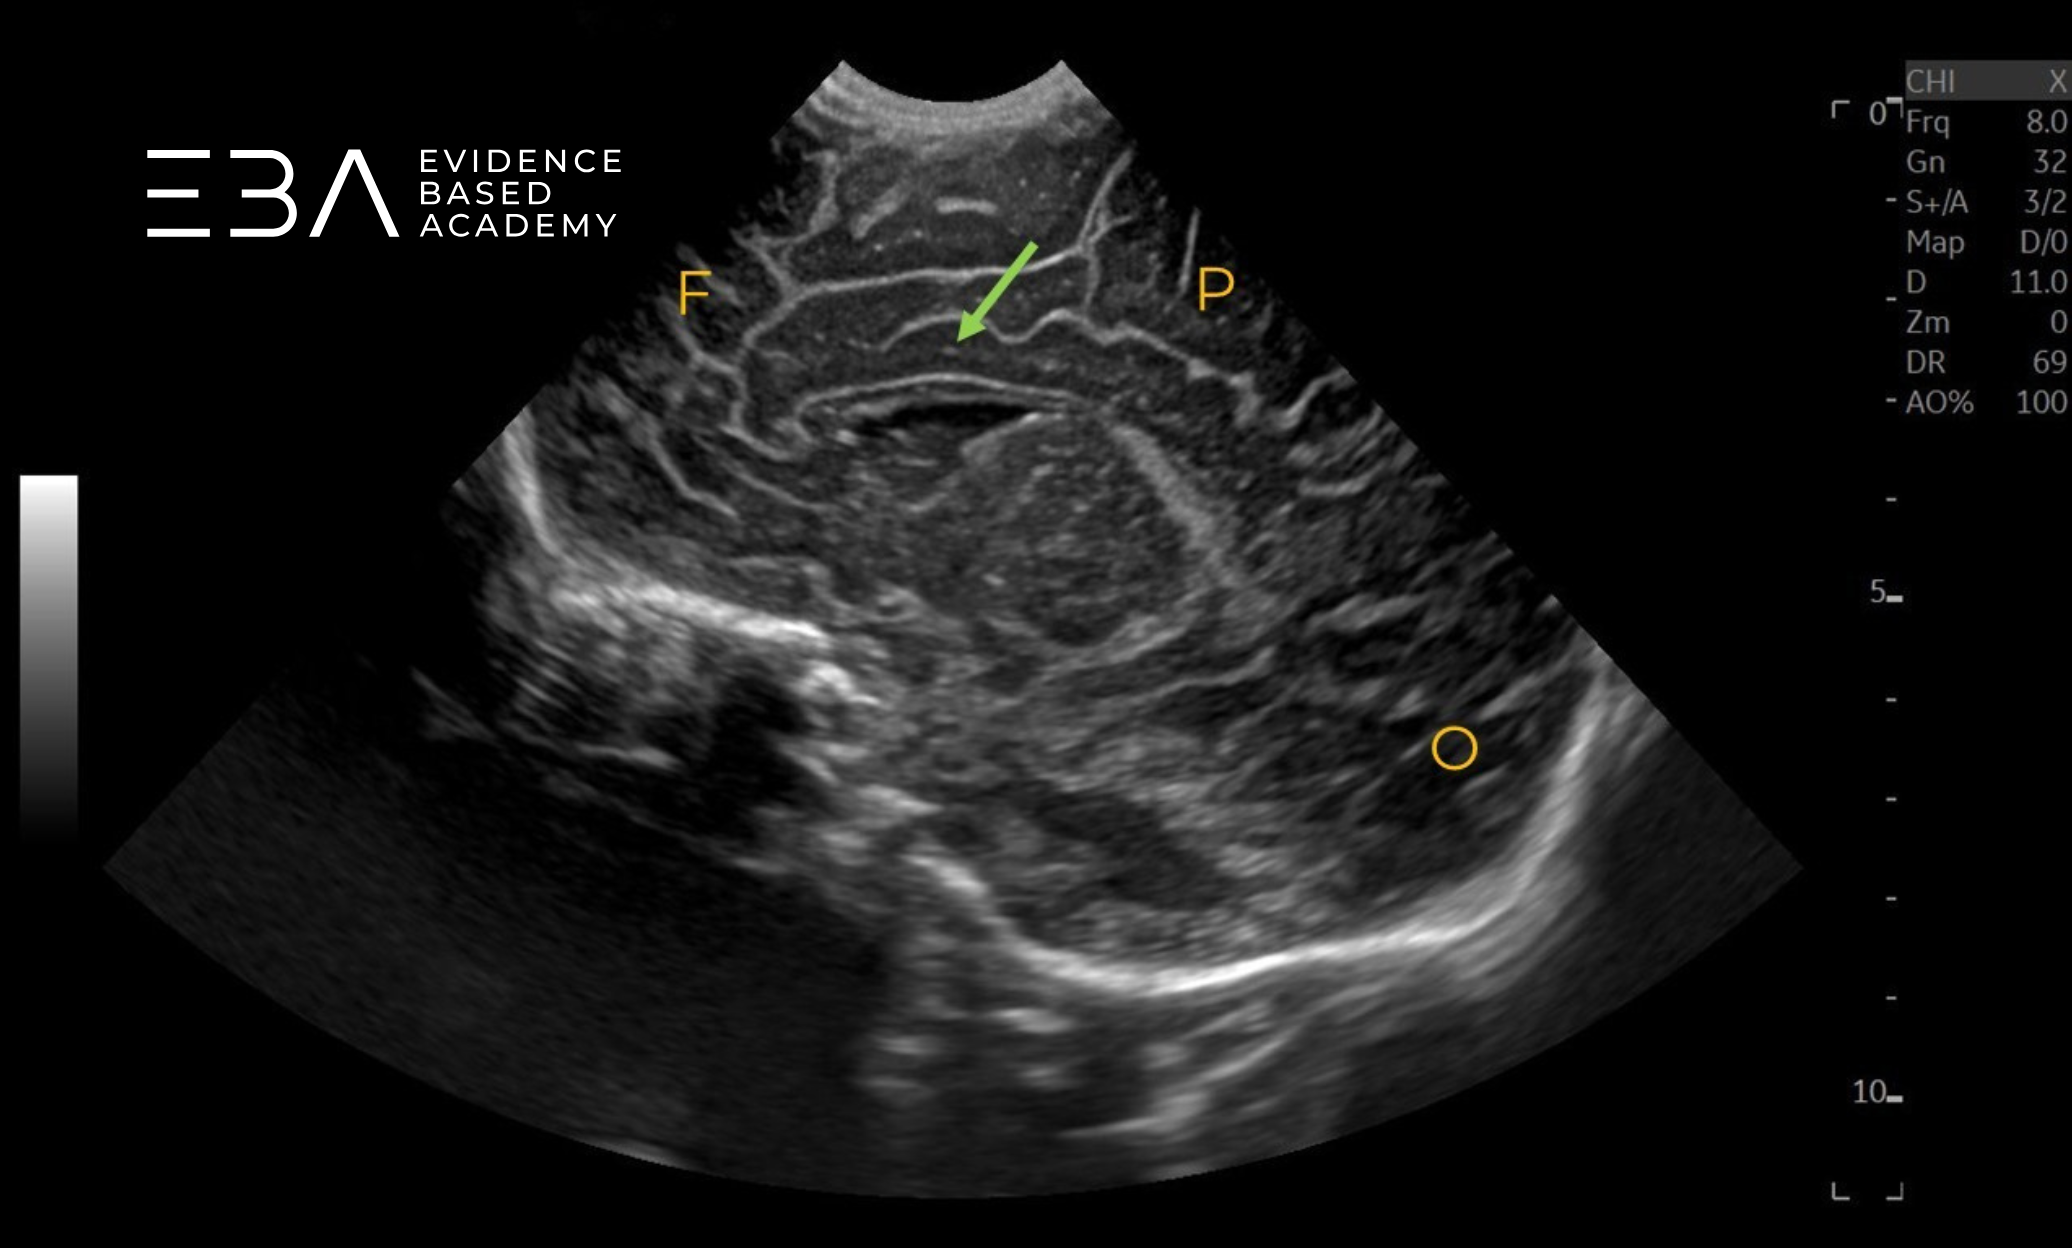

zdj. 17

Głowica liniowa – projekcja przystrzałkowa. F – płat czołowy, P – płat ciemieniowy, O – płat potyliczny. Strzałką zaznaczono zakręt obręczy.